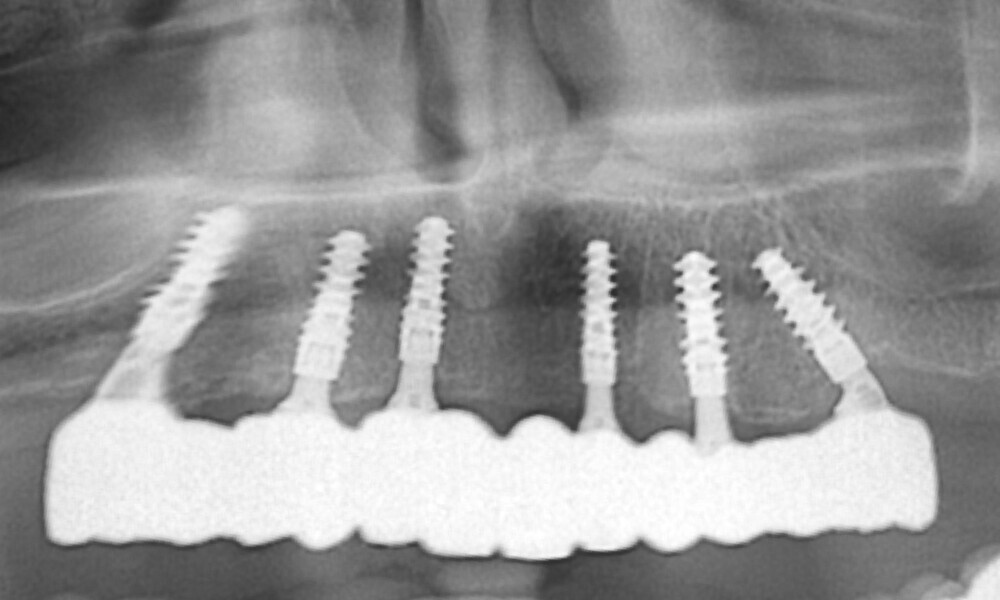

The fit of the previously sterilised provisional guide and surgical guide was then verified (Figs. 21 & 22). The surgical guide was positioned, aligning it with the arch and extraction sockets. Subsequently, the holes for the anchor pins were drilled and the pins inserted (Figs. 23 & 24). The surgery was initiated using a mucosa punch at 15 rpm through the sleeves of the surgical guide. This method allowed for blade-free incision with minimal trauma (Figs. 25 & 26). After removing the mucosal punch, the surgical guide was reinserted to begin the placement of the implants (Fig. 27). The surgical protocol, provided alongside the surgical guide, recommended the sequence of instruments required to prepare each implant site. The osteotomy sites were prepared following the manufacturer’s recommended drilling protocol using a copious amount of saline irrigation, and the implants placed as follows and parallelism checked (Figs. 28–31):

• position #16: 5 × 12.0 mm; regular base (RB);

• position #14: 0 × 12.0 mm; RB;

• position #12: 0 × 12.0 mm; RB;

• position #22: 0 × 12.0 mm; RB;

• position #24: 5 × 12.0 mm; RB; and

• position #26: 5 × 12.0 mm; RB.

Screw-retained abutments (Straumann) were placed to a torque of 35 N cm as follows (Figs. 32 & 33):

• position #16: RB/wide base (WB); 30°; diameter: 6 mm; gingiva height: 3.5 mm;

• position #14: RB/WB; 17°; diameter: 6 mm; gingiva height: 3.5 mm;

• position #12: RB/WB; 17°; diameter: 6 mm; gingiva height: 3.5 mm;

• position #22: RB/WB; 17°; diameter: 6 mm; gingiva height: 3.5 mm;

• position #24: RB/WB; straight; diameter: 6 mm; gingiva height: 3.5 mm; and

• position #26: RB/WB; 30°; diameter: 6 mm; gingiva height: 3.5 mm.

The delivery of the final prosthesis was then performed, and the aesthetics, occlusion and function were verified (Figs. 51–55). The panoramic control radiograph showed that all measurements were within expected ranges (Fig. 56).